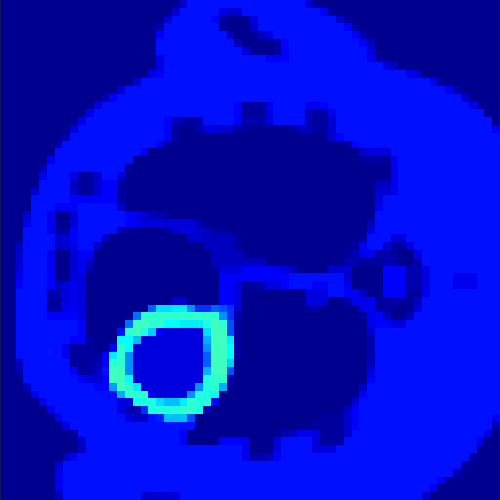

5.2 Monte Carlo Simulation

In order to test the behaviour of the proposed method in a more realistic, random-based test case, we performed a Monte Carlo simulation for dynamic SPECT imaging. First, we created a simple image phantom consisting of an outer and two inner circles which represents the structure of the region of interest (see figure 8(a)). Within those regions we assumed concentration curves over a time period of 90 time steps as displayed in figure 8(b). Based on the tracer intensity in an image frame at each time step, we created a variable number of random decay events (where the number is proportional to the average concentration in one pixel in the whole image frame per time step) with a probability proportional to the concentration in every subregion. They are detected by a virtual double head gamma camera rotating around the patient by 46 degrees per time step, which consists of 374 detector bins. Every simulated decay event is projected onto the scanner and counted by the corresponding detector bin.

In two different tests we fixed the number of events counted by the detector equal to (resp. ) times the average concentration in one pixel. The resulting sinogram images of the accumulated counts in each bin are shown in figure 9.

Based on the sinogram data we applied the proposed algorithm in order to reconstruct the original image sequence. The results for both test cases are shown in figure 10.

As one can see, the method is able to reconstruct the regions properly, even in case of a low count number. Within a number of iterations (average of 100 outer and 10000 inner iterations), the algorithm presents a reasonable reconstruction of the region of interest and the corresponding regional tracer concentration curves. Here, the parameters were not optimized as in the case of the synthesized data sets in the previous section, but kept fixed as , and . With futher optimized parameter values one could possibly provide even better results.